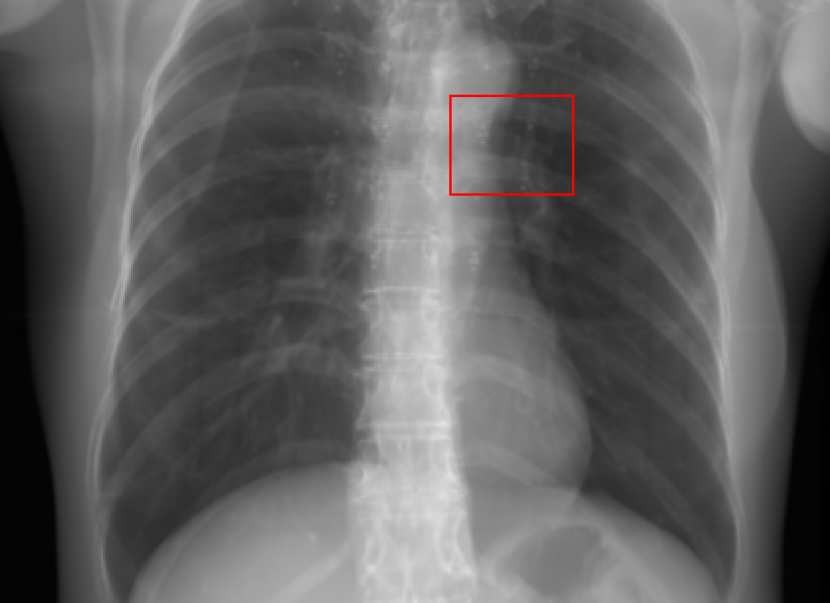

Refer to caption

(a) Reference

(b) 0superscript00^{\circ} perspective

(c) (b)-(a)

0.4237, -, -

0.4002, 17.01, 0.6532

Pix2pixGAN

(d) 0superscript00^{\circ} Cartesian

(e) 0&180superscript0superscript1800^{\circ}\&180^{\circ} Cartesian

(f) 0&180superscript0superscript1800^{\circ}\&180^{\circ} polar

0.4303, 7.08, 0.8535

0.4214, 5.37, 0.9098

0.4240, 3.83, 0.9536

(g) (d)-(a)

(h) (e)-(a)

(i) (f)-(a)

TransU-Net

(j) 0superscript00^{\circ} Cartesian

(k) 0&180superscript0superscript1800^{\circ}\&180^{\circ} Cartesian

(l) 0&180superscript0superscript1800^{\circ}\&180^{\circ} polar

0.4272, 10.92, 0.8222

0.4281, 9.37, 0.8424

0.4248, 8.12, 0.8859

(m) (j)-(a)

(n) (k)-(a)

(o) (l)-(a)

Figure 10: Perspective deformation learning in one exemplary patient case for chest X-ray imaging. The maximal horizontal cardiac diameter and the maximal horizontal thoracic diameter in (b) and (d)-(f) are indicated by the horizontal red lines, while those in the reference image (a) are green lines. The cardiothoracic ratio, RMSE, and SSIM for each image is displayed in its corresponding subcaption.

The results of one patient in chest X-ray imaging are displayed in Fig. 10, where the cardiothoracic ratio is assessed as an exemplary clinical application [32]. In the reference image (Fig. 10(a)), the maximal horizontal cardiac diameter (MHCD) and the maximal horizontal thoracic diameter (MHTD) are indicated by two green horizontal lines. Its cardiothoracic ratio is 0.4237. In the 0superscript00^{\circ} perspective projection image (Fig. 10(b)), all the anatomical structures can be visualized with fine resolution. However, due to perspective deformation, anatomical structures, e.g. the ribs and the spine, are deformed. The deformations are visualized better in the difference image Fig. 10(c). Compared with the ribs and the spine, the heart has less deformation as its location is closer to the isocenter. In Fig. 10(b), the MHCD and the MHTD are indicated by two red horizontal lines, while the green lines are those of the reference image. While the MHCD has changed little from 10.47 cm to 10.16 cm, the MHTD has changed considerably from 24.71 cm to 25.40 cm. As a consequence, the cardiothoracic ratio becomes 0.4002, which is below the normal range of 0.42 - 0.50 [32]. The result of learning perspective deformation from 0superscript00^{\circ} single view is displayed in Fig. 10(d), where the MHCD and the MHTD are 10.63 cm and 24.71 cm, respectively. The MHTD of Fig. 10(d) is the same as that of the reference image. This is also reflected by the difference image Fig. 10(g), where the lower ribs have small errors. However, the upper ribs as well as the spine still have considerable errors. The results of perspective deformation learning from 0&180superscript0superscript1800^{\circ}\&180^{\circ} views in Cartesian and polar coordinates are displayed in Fig. 10(e) and Fig. 10(f), respectively. The measured MHCDs and MHTDs in these two images are very close to the reference ones. Hence, their cardiothoracic ratios, 0.4214 and 0.4240 respectively, are close to the reference ratio as well. In the difference images (Fig. 10(h) and Fig. 10(i)), the errors of ribs and spine decrease as their boundaries are no longer apparently visible. Nevertheless, Fig. 10(i) has less error than Fig. 10(h), achieving the smallest RMSE value of 3.83. The quantitative evaluation of all the 162 testing datasets is displayed in Tab. II, where learning perspective deformation from two complementary views in polar coordinates achieves the least RMSE 4.98 and highest SSIM 0.9517, demonstrating the superiority of learning perspective deformation from two complementary views in polar coordinates.

The TransU-Net results are displayed in Figs. 10(j)-(l). Compared with their corresponding Pix2pixGAN results, the TransU-Net prediction images are more blurry, although the same perceptual loss is used. The error images in Figs. 10(m)-(o) indicate that TransU-Net reduces perspective deformation better with complementary views than a single view. The quantitative evaluation in Tab. II shows that TransU-Net cannot effectively reduce perspective deformation with a single view. With complementary views in both Cartesian and polar coordinate systems, TransU-Net achieves comparable performance, which is still considerably worse than that of Pix2pixGAN. The inferior performance of TransU-Net to Pix2pixGAN on the chest data is potentially caused by the repetitive nature of the segmental rib anatomy, which leads TransU-Net to be ineffective in extracting position-dependent features.